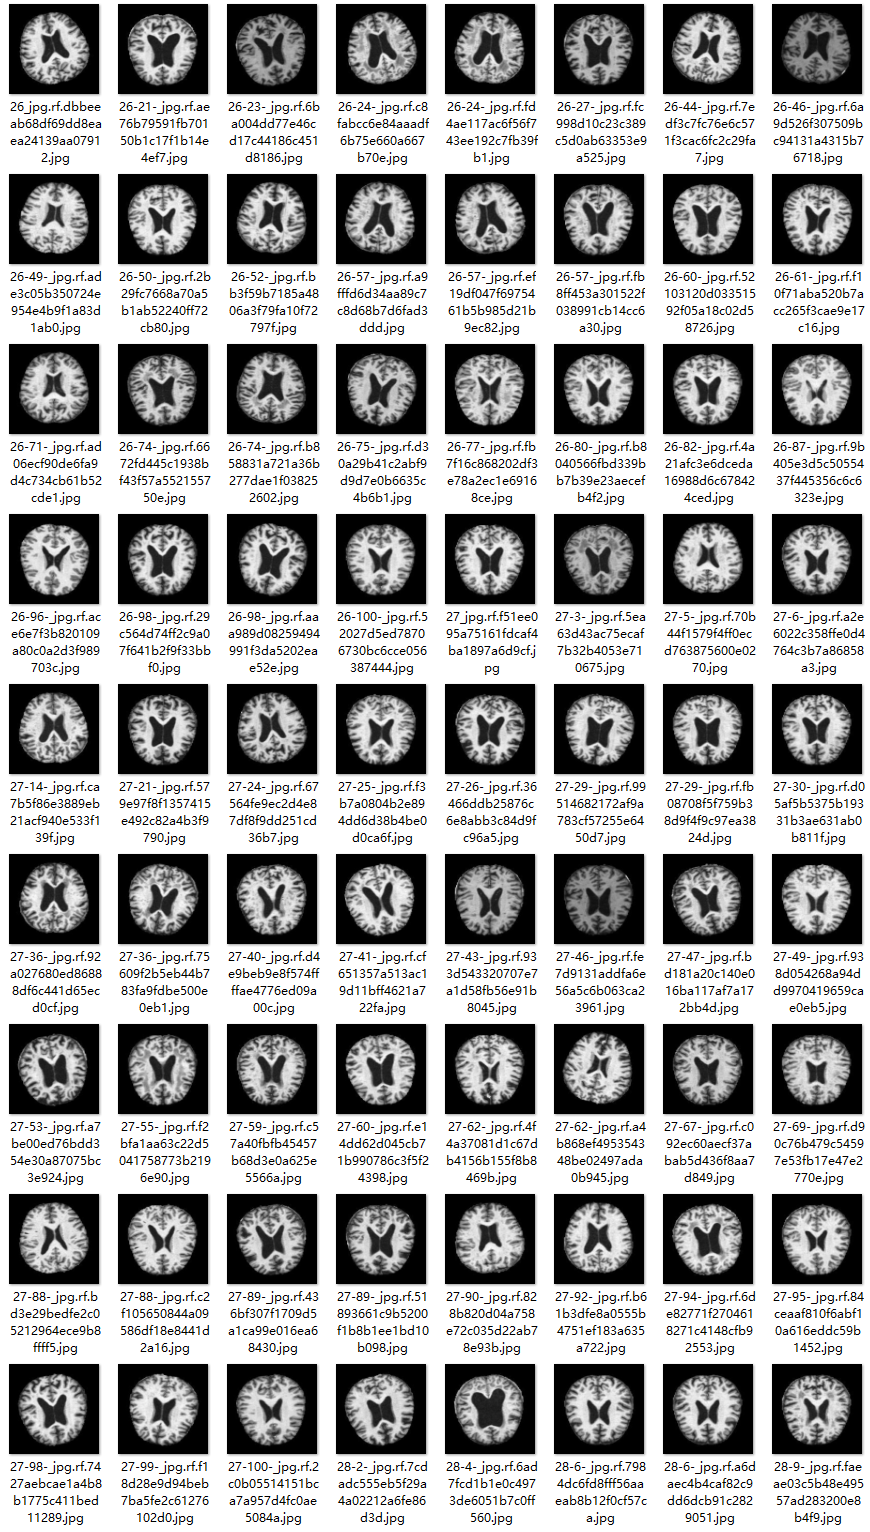

本研究采用了涵盖多种老年痴呆症相关图像的数据集,并借助Labelimg标注工具对每张图像中的目标边界框(Bounding Box)及其类别进行了精确标注。随后主要基于YOLOv8n模型构建了训练框架,在完成模型训练后对验证集的表现进行了全面分析和对比研究。整个模型开发流程包括:数据准备、模型构建与训练、性能评估三个阶段。具体而言,在本次研究中所涉及的目标分类仅限于老年痴呆症这一类别,在数据集中共有3288张图片参与其中,其中用于训练的数据占2572张,在验证集中选取了716张图片进行测试分析。如图所示的部分图片展示了典型的老年痴呆症相关图像样本